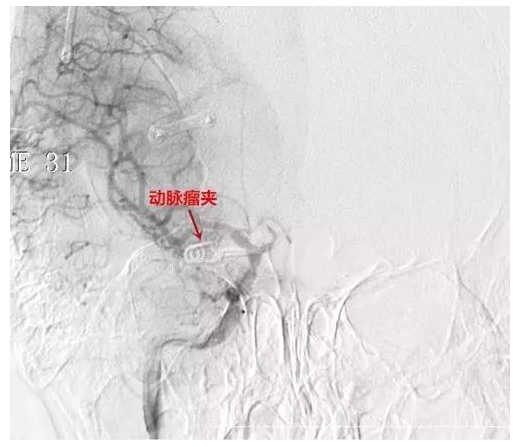

术后▲

手术由神经外一科主任张良博士主刀完成,完善术前检查后,在全麻下行“右侧后交通动脉瘤夹闭术”,经系统治疗后患者颞部疼痛及眼睑下垂症状较前缓解康复出院。

后交通动脉瘤的治疗主要采用开颅动脉瘤夹闭术和血管内栓塞术,血管内栓塞术具有微侵袭及并发症少等优势,是治疗颅内动脉瘤的主要手段,显微手术治疗的优势在于:对于动脉瘤破裂伴有颅内血肿、颅内压明显增高者,手术能清除血肿,甚至必要时可去除骨瓣,以缓解颅内高压;手术可以清除蛛网膜下腔出血,也有利于防止术后脑血管痉挛和改善患者的症状;手术在夹闭动脉瘤颈的同时,可以解除动脉瘤造成的占位效应]。后交通动脉瘤造成的动眼神经麻痹,直接手术完全恢复率为71.8%,而介入手术仅为35.7%。此例患者未有蛛网膜下腔出血,颅内压不高,但存在动眼神经麻痹,采用开颅显微手术治疗,术后症状也较前恢复,取得理想效果。